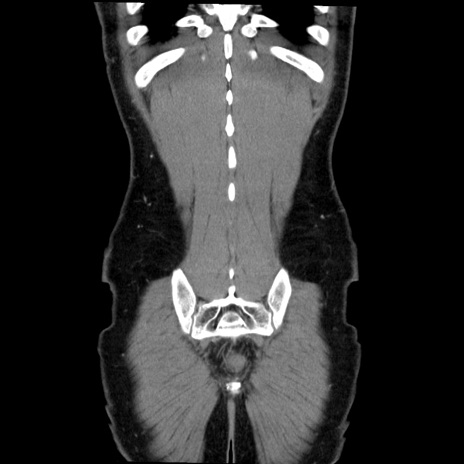

症例36(冠状断像)

【症例】20歳代 男性

【主訴】心窩部痛

【現病歴】今朝より上腹部痛あり。一旦軽快していたが再度出現したため救急要請。昨日夕に白身の魚を含む刺身を食べた。

【身体所見】BP 136/89mmHg、HR 74/min、BT 37.0℃、腹部:膨満、軟、心窩部に圧痛あり。反跳痛なし、筋性防御なし、腸雑音やや亢進あり。

【データ】WBC 17700、CRP 0.48